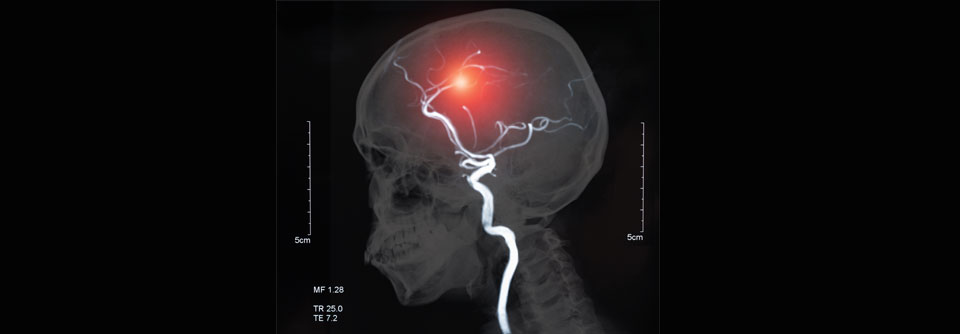

Nach jeder transitorischen ischämischen Attacke steht wie bei diesem 93-Jährigen die gründliche Untersuchung an. Nach jeder transitorischen ischämischen Attacke steht wie bei diesem 93-Jährigen die gründliche Untersuchung an. © Science Photo Library/Reeve, Antonia

Wer eine transitorische ischämische Attacke hinter sich hat, ist hochgefährdet, bald einen „richtigen“ ­zerebrovaskulären Insult zu erleiden. Experten der American Heart Association geben Empfehlungen, was bei Patienten mit einem solchen Mini-Schlaganfall zu tun ist.

In den 90 Tagen nach einer transi­torischen ischämischen Attacke (TIA) beträgt das Risiko für einen Schlaganfall zwischen 10 % und 18 %. Die Hälfte der Hirninfarkte tritt schon in den ersten zwei Tagen nach der TIA auf.

Die Diagnostik dieser passageren zerebralen Ischämie ist im Alltag gar nicht so einfach, schreibt ein Autorenteam der American­ Heart­ Association­ (AHA) in einem Scientific­ Statement­. Denn per definitionem­ sind die Symptome einer TIA spätestens nach 24 Stunden verschwunden, oft halten sie kaum länger als eine Stunde an, erläutern Dr. Hardik­ Amin­ und Kollegen. Auch in der MRT mit DWI*-Sequenzen sind 24 Stunden nach dem Ereignis keine Spuren mehr sichtbar.